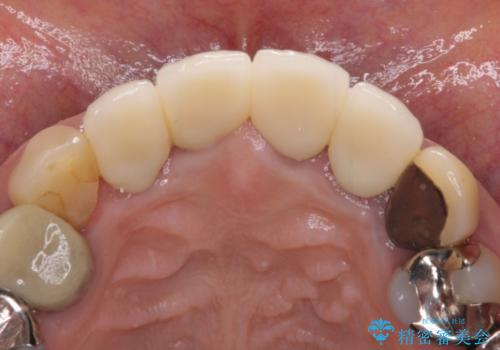

金属の土台を歯の色に近いものへと変更した上で、オールセラミッククラウンにて補綴することとしました。

自然で透明感のある前歯になると同時に、歯茎付近の黒ずみや隙間も改善でき、患者様には大変満足していただきました。